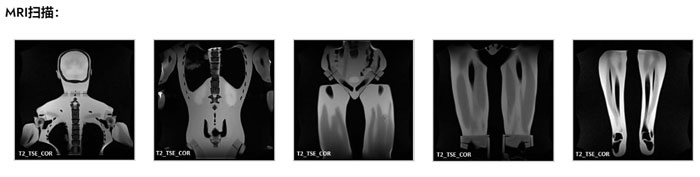

FB-A02成人全身模體,FB-A02全身CT模型成像效果圖如下:

FB-A02成人全身模體,FB-A02全身CT模型成像效果圖

Adult Full Body Phantom是一款兼容 X 射線/CT 和 MRI 的訓(xùn)練產(chǎn)品。該模型的主要應(yīng)用是訓(xùn)練和演示放射學(xué)中的各種患者定位技術(shù)。其他用途包括診斷成像技術(shù)和視覺評估的實踐經(jīng)驗,以找到最佳掃描條件。

在 MRI 應(yīng)用方面,模型組織具有真實的 T2 弛豫時間值,這使得該產(chǎn)品最適合任何 T2 加權(quán) MRI 成像方法。質(zhì)子密度成像方法也可以獲得非常好的結(jié)果。模型仍然可以使用 T1 加權(quán)方法成像,但 T1 值不太真實,并且在大約 100 毫秒的范圍內(nèi)。